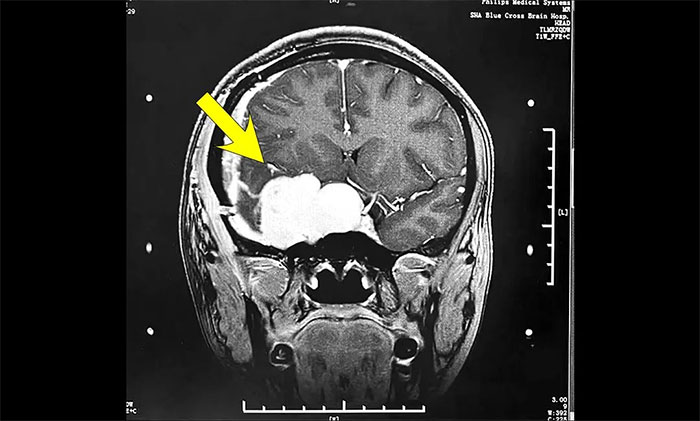

陳琦主任團(tuán)隊(duì)根據(jù)患者病情,精心設(shè)計(jì)了分期治療的靶區(qū)和治療劑量,用伽瑪射線聚焦于病灶,使病變組織凋亡并逐漸阻斷血供,從而達(dá)到治療目的。完成治療后患者順利出院,半年后來院復(fù)查,病灶較前明顯縮小。

▲ 治療后病灶明顯縮小